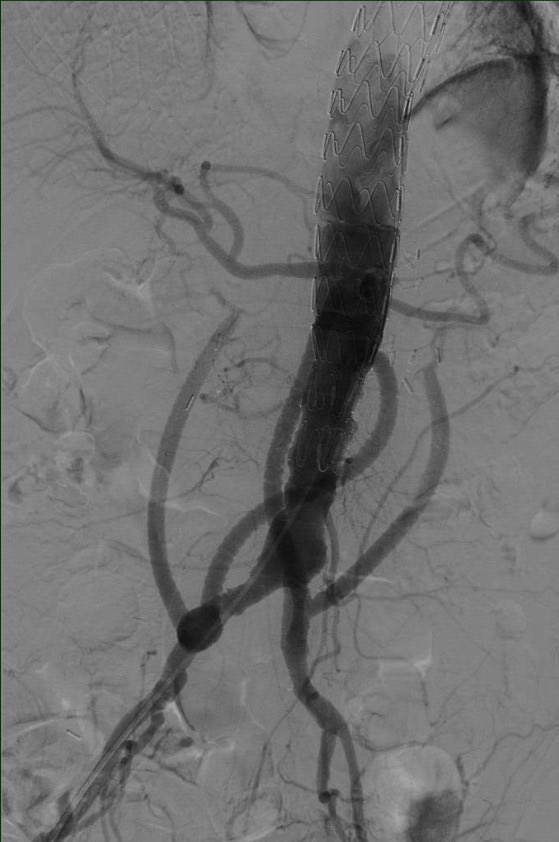

A 62/M COPD pt with Type 5 TAAA under went Hybrid TEVAR. Link for surgery in this link -youtu.be/cVKjV5J8YFk